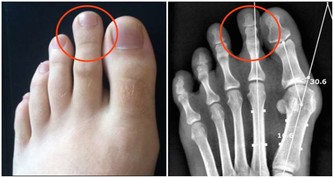

“空調腿”是指室內開啟空調後,地面水平溫度最低,人的雙腿長期低暴露在外,

容易受涼刺激,出現雙腿酸痛,嚴重時膝關節疼痛、腫脹,使人難以忍受。

絕大多數“空調腿”是膝關節受寒冷刺激導致的滑膜炎、滑囊炎以及腿部肌肉受冷痙攣。

當人體遇冷時,血管收縮,血流速度減慢,血液中輸送的人體所需的各種養料和氧氣就會減少,而膝關節支撐人的身體,本身周圍血管少,血流速度就差,若穿著短褲、短裙則會使膝關節暴露在低溫環境,膝關節長時間受寒涼刺激,血液循環更慢,更易出現水腫和炎症改變,導致滑囊炎、滑膜炎等關節性疾病。